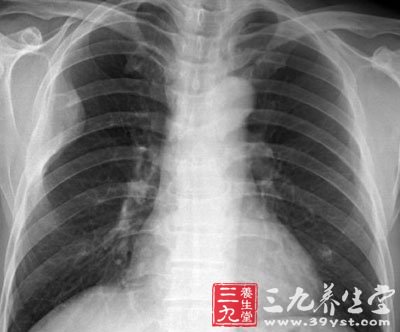

(一)X线胸片,为肺纹理增多,肺实质可有多形态的浸润形,以下叶多见,也可,呈斑点状,斑片状或均匀模糊阴影。约1/5有少量胸腔积液。